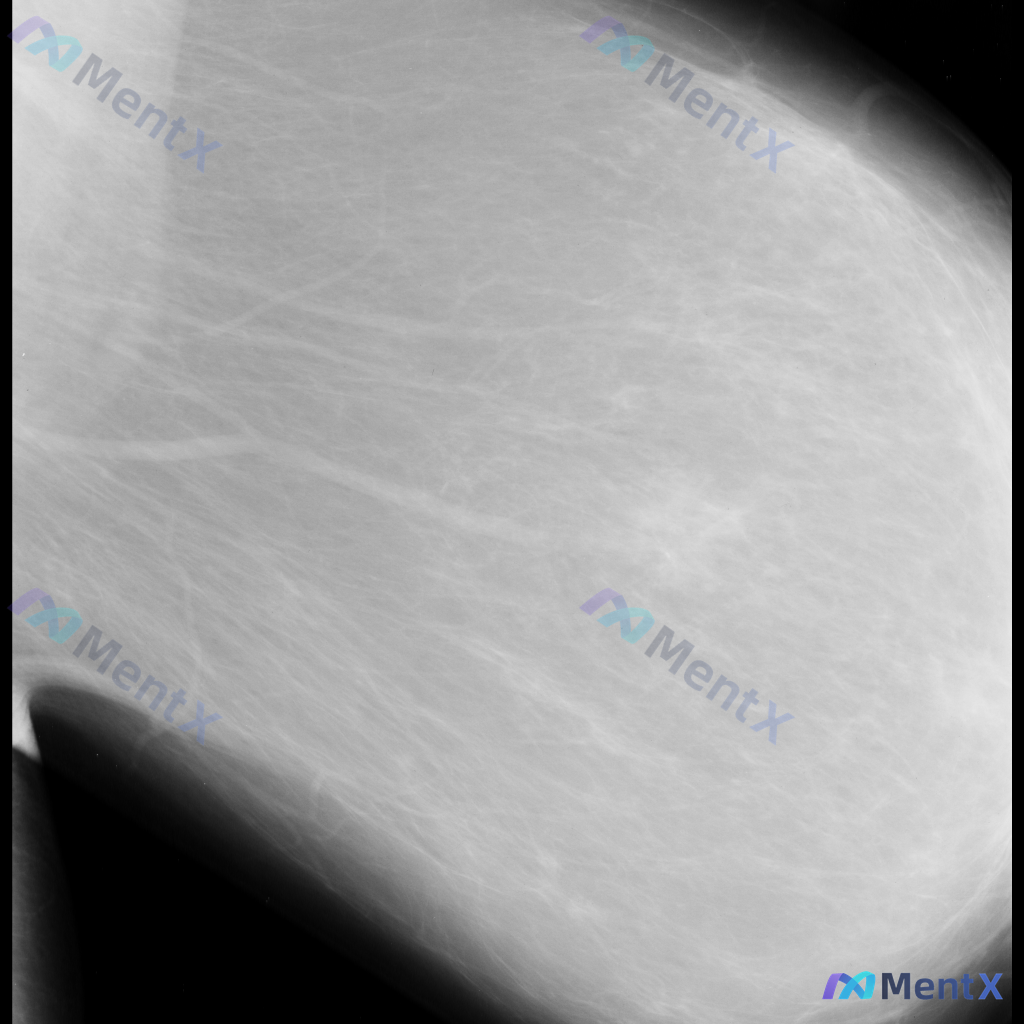

整理到一份单张的乳腺钼靶影像资料,仅有单侧、单幅图像,没有对侧对照,也不确定是MLO位还是CC位。 目前能看到的信息大概是: - 乳腺类型看起来是多量腺体型 - 图像上没有看到明确的肿块、可疑的恶性钙化 - 皮肤、乳头、血管这些能看到的部分没有明显异常(不过图像范围没包含腋窝) 这种情况下,大家觉得...

整理到一份乳腺钼靶的影像资料,先和大家讨论一下读片思路。 基本影像信息 - 图像类型:单张乳腺钼靶侧位片(具体投照体位未明确,无对侧对比) - 乳腺构成:不均匀致密型(ACR C型),腺体密度较高 目前可见的影像表现 - 图像中部偏外侧的纤维腺体组织结构走行略显紊乱,但不足以诊断为明确的结构扭曲 -...